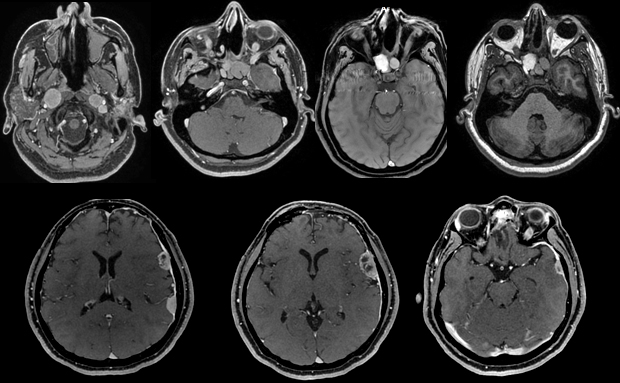

M. Alberto Gonzalez-Aguilar Instituto Nacional de Neurología y Neurocirugía - Paris

• Femme de 45 ans sans antécédent adressée pour hyposmie progressive (2 mois) et déficit moteur droit.

• A l’examen aux urgences, il est noté une hémiparesie droite discrète.

• Une IRM est réalisée en urgence.

Quels diagnostics évoquez-vous ?